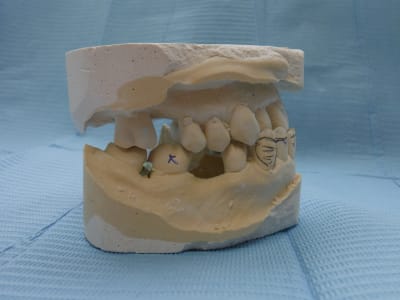

sans commentaire.

Ah si! 64 ans... et 41, 31 HS...

Lui 59 ans, 41 HS, c'est la semaine!!! les photos ne sont pas tops :-(